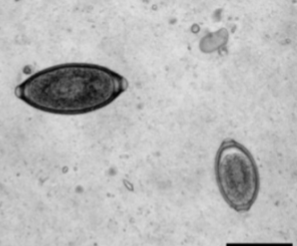

Eucoleus aerophilus

Capillarid lungworm of dogs and cats

where is Eucoleus aerophilus located in host

adults are located in bronchi and trachea

is Eucoleus aerophilus zoonotic

yes

Eucoleus böehmi

Respiratory capillarid of dogs

where is Eucoleus böehmi located in host

adults are located in nasal cavities and sinuses

are Eucoleus böehmi zoonotic

nope